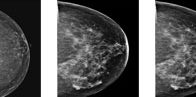

Screening Breast Ultrasound also known as Automated Breast Ultrasound (ABUS) is a test for women who have known dense breast tissue. . A Smarter Way to See Through Density Detecting cancer through dense breast tissue is challenging! Dense breast tissue and cancers show up as white on a mammogram, making it easy for cancer to…